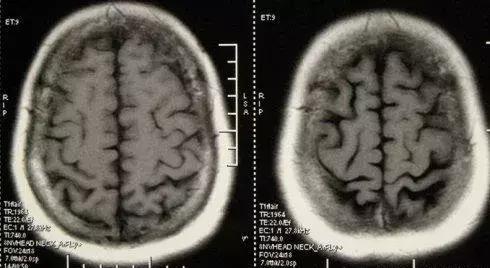

02小脑萎缩是什么?

小脑萎缩并不是指某一种疾病,而是退行性病变。它在老年人中更常见,可能与年龄增长(衰老)或疾病有关。如果小脑萎缩,人的协调性和平衡能力都会受到影响。